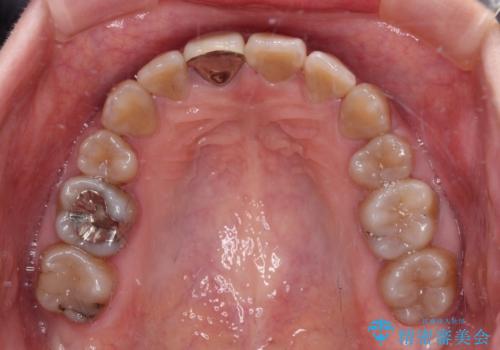

八重歯とクロスバイト 目立たないワイヤー装置での抜歯矯正

- 八重歯や前歯のデコボコを気にして来院された患者様です。

歯列が前方に傾斜しており、デコボコが強かったため、上下左右第一小臼歯4歯を抜去し、ワイヤー装置による矯正治療を行うこととしました。

上下の正中がずれていましたが、抜歯矯正であったので、極力正中位置を合わせるように治療を進めて行きました。

顎間ゴムの使用などにより、正中位置を改善することができました。